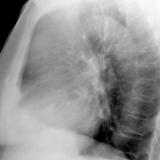

Thymic carcinoma Lat

Date: 08/15/2012

Views: 10191